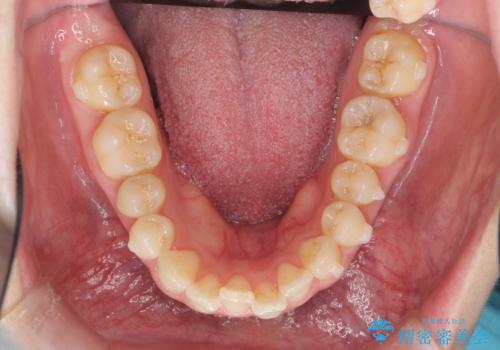

マウスピース 狭窄歯列の改善

- 噛み合わせが深い、笑った時の歯並びの改善を求めて来院されました。

マウスピース型の矯正装置インビザラインを用いた治療を計画します。

狭くなってしまった歯並びを放物線状に並べることで噛み合わせの安定・見た目の改善・ガタつきの改善を達成することができました。